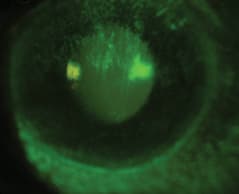

Figure 6 shows the FK with fluorescein dye. Figure 7 shows the same eye after having worn the MSD lens for about four-and-one-half hours. Note the decrease in conjunctival injection, the absence of FK, and the absence of limbal vessel compression.

Figure 6. Filamentary keratitis following a GVHD flare-up.

Figure 7. Resolution of filamentary keratitis after four hours of custom MSD wear.